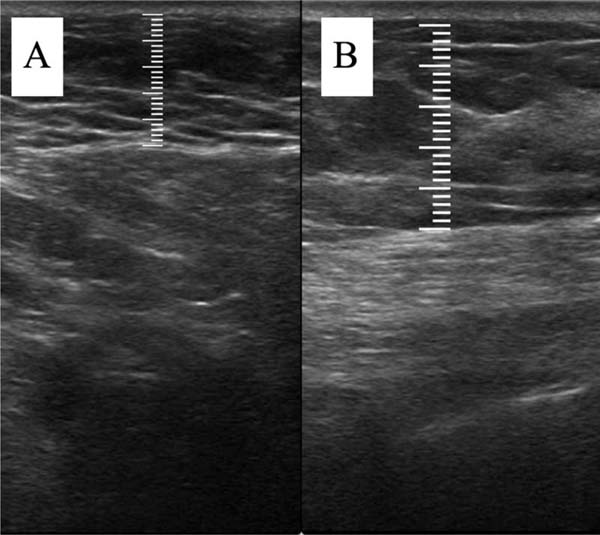

Within the breast quadrant with perceived low volume, a fixed point is established for measuring subcutaneous thickness during follow-up. This point defines the central region of the quadrant, and the shortest distances from it to the clavicle and to the nearest division of the breast quadrant are recorded for reproduction in subsequent measurements (►Fig. 1).

Ultrasound assessment

The measurement of subcutaneous tissue thickness is performed vertically, from the highest (right at the transition from the epidermis) to the lowest point (at the transition with the muscle tissue) of subcutaneous tissue thickness. This measurement is easily reproducible for those with basic ultrasound skills (►Fig. 2). In lipofilled breasts, the thickness of subcutaneous tissue was measured preoperatively and immediately after lipofilling, as well as at 15, 30, 90, and 180 days postoperatively. Measurements in millimeters were taken using ultrasound, including the vertical distance from the highest (closest to the epidermis) to the lowest point (closest to the adjacent musculature) of the subcutaneous tissue at the previously defined point. A GE LOGIQ P6 (GE HealthCare) ultrasound device with an 11L linear probe and a frequency range of 12 to 6 MHz was used, operated by a surgeon with postgraduate training in general ultrasonography (►Fig. 3).